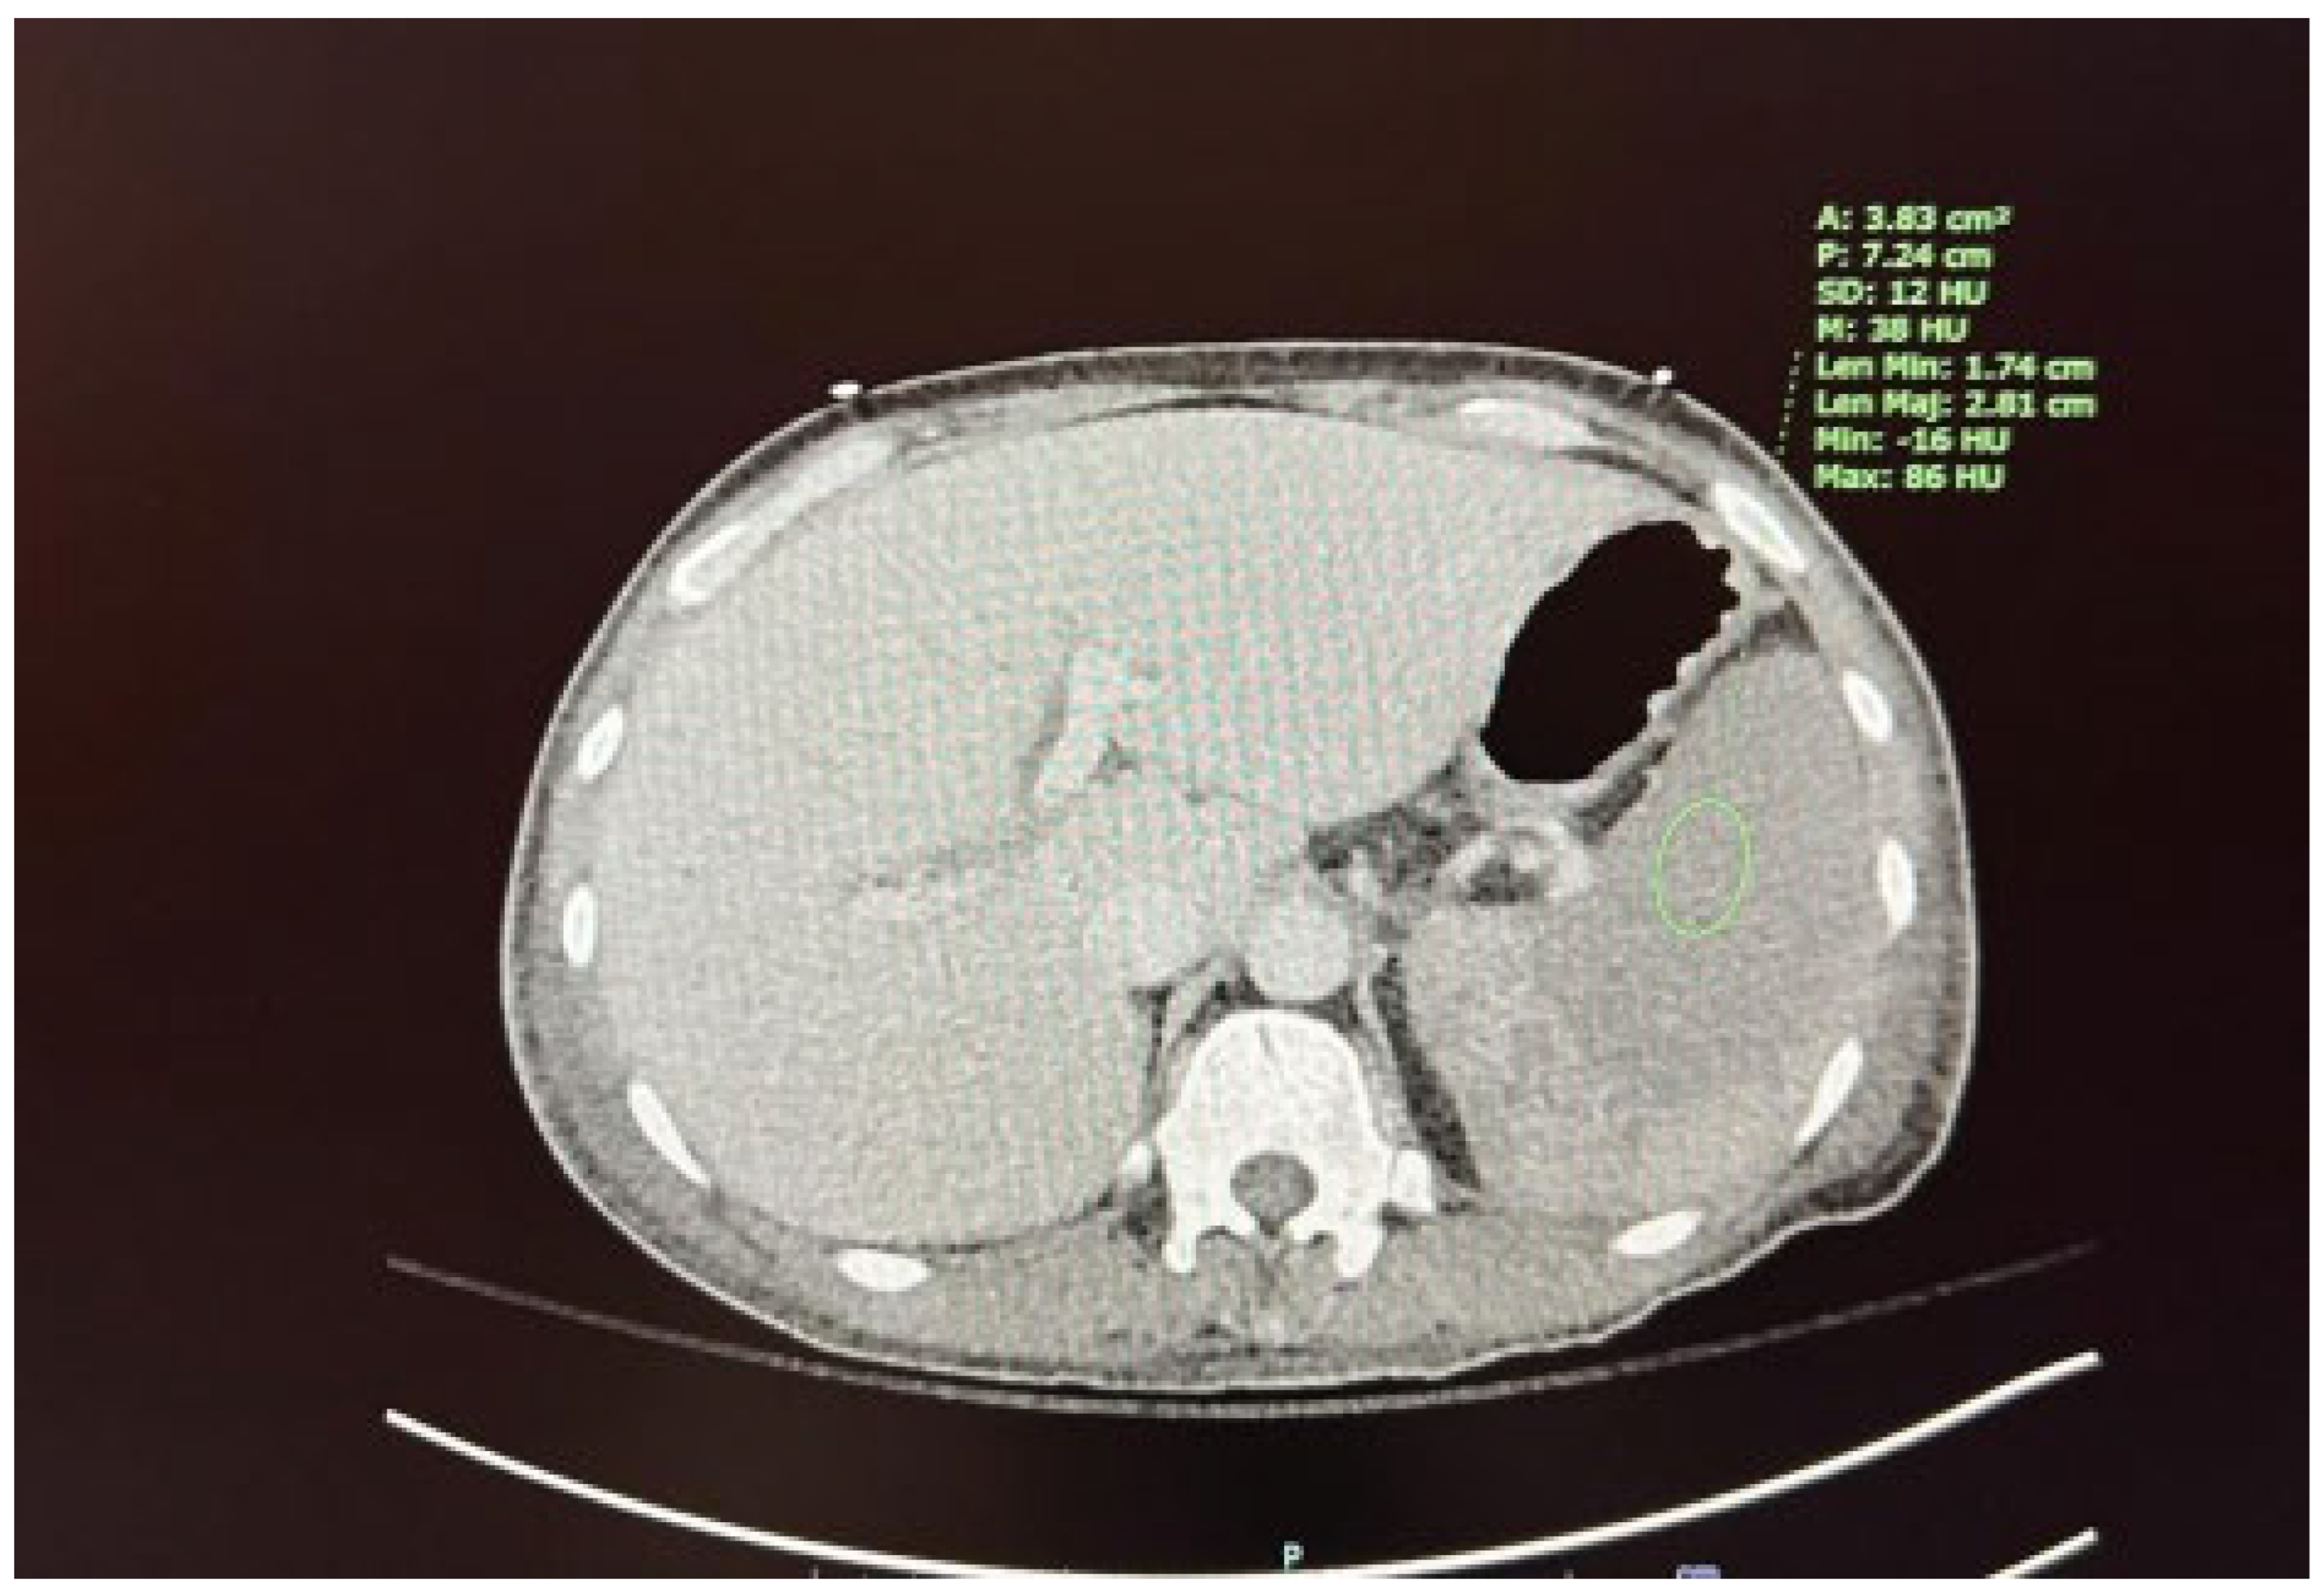

We present the case of a 67-year-old male diagnosed with high-risk chronic myelomonocytic leukemia (CMML) in October 2023. The patient presented to the hematology/oncology clinic exhibiting symptoms of malaise, dizziness, chills, tachycardia, and hypotension, which raised concerns about sepsis. Following the administration of 1 liter of intravenous fluids and cefepime, he was subsequently referred to the emergency department. Upon admission to the medicine floor, he underwent evaluation and management for sepsis and lactic acidosis. However, due to persistent hypotension necessitating vasopressor support and elevated lactic acid levels greater than 5 mmol/L, he was transferred to the medical intensive care unit. This admission marked the patient’s fourth instance of neutropenic fever since the initial diagnosis of CMML. His condition was further complicated by a peripheral blast crisis, prompting treatment with azacitidine and venetoclax, as well as the presence of pancytopenia accompanied by leukocytosis (now showing a downtrend) and severe thrombocytopenia, placing him at risk for tumor lysis syndrome. The patient had recently received chemotherapy on April 5, 2024, as well as Neulasta on April 8, 2024, for neutropenic support. He reported experiencing severe abdominal pain, rated at 8 out of 10. A computed tomography (CT) scan conducted on April 10, 2024, discounted the existence of an infectious focus and indicated hepatosplenomegaly, alongside diffuse low-density lesions in the spleen suggestive of a developing splenic infarct and minimal peri-splenic fluid accumulation; however, no active bleeding was detected (see Figure 1 and Figure 2). The critical illness of the patient appeared to be associated with the underlying CMML, recent chemotherapy, and complications from treatment, including splenic infarction, potentially attributable to the use of filgrastim.

Figure 2. Diffuse low-density lesions in the spleen consistent with a developing splenic infarct.